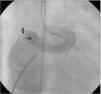

The patient was referred for a diagnostic cardiac catheterization. Angiography confirmed a coronary fistula measuring 13 mm in diameter at the aortic end and draining into the right atrium (RA) through at least two small openings (Figure 1). The left anterior descending (LAD) and circumflex (Cx) arteries originated in the proximal extremity of the fistula through two separate orifices. Catheterization showed normal right and left heart pressures, oxygen saturation step-up in the right atrium and Qp:Qs of 1.7. Informed consent was obtained and percutaneous closure of the fistula was attempted using a 16 mm Amplatzer® vascular plug II (AGA Medical). Through a femoral approach, a 7 Fr venous and a 6 Fr arterial sheath were used. A 6 Fr Concierge Amplatz Left 2 guiding catheter was positioned in the aorta at the fistula entrance and a 0.035 in Terumo® hydrophilic guide wire was advanced along the fistula, until the right atrium was reached. The wire was then snared and an arteriovenous (AV) loop was created. A 7 Fr Amplatzer Delivery System was used to deploy the device through the atrial end (Figure 2). A significant residual shunt was observed after deployment of the device. Cardiac enzymes were within normal range and the ECG showed no abnormalities. After this procedure anticoagulation was prescribed for six months and aspirin maintained thereafter.